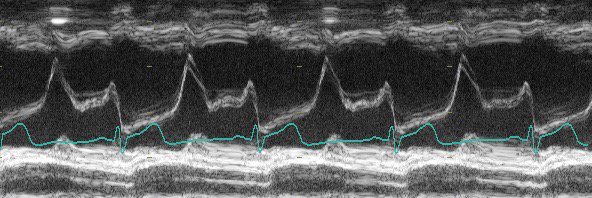

Check out the #SPEED Protocol on @TheSGEM. I feel the need, the need for SPEED to diagnose AoD!

thesgem.com/2024/03/sgem43… @TempleEM @templemedschool @TempleHealth @jeff_sono @PennUltrasound @AcademicEmerMed @SAEMonline @SAEMAEUS @ACEP_EUS @AIUMultrasound onlinelibrary.wiley.com/doi/10.1111/ac…